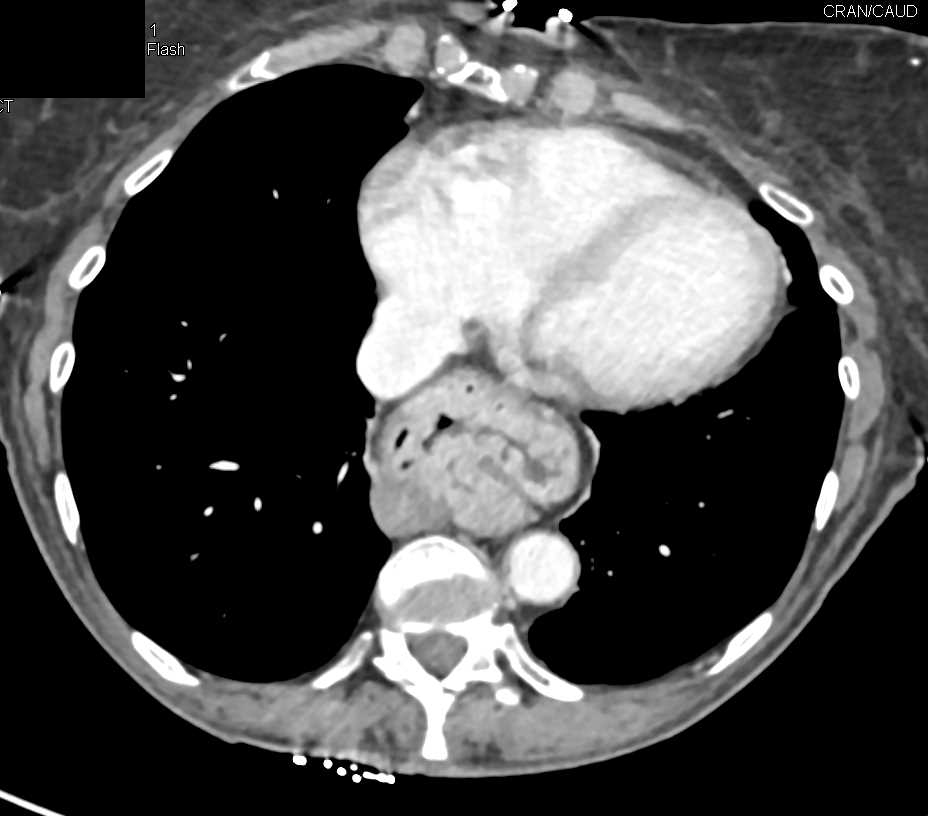

Metastatic Renal Cell Carcinoma to the Pancreas